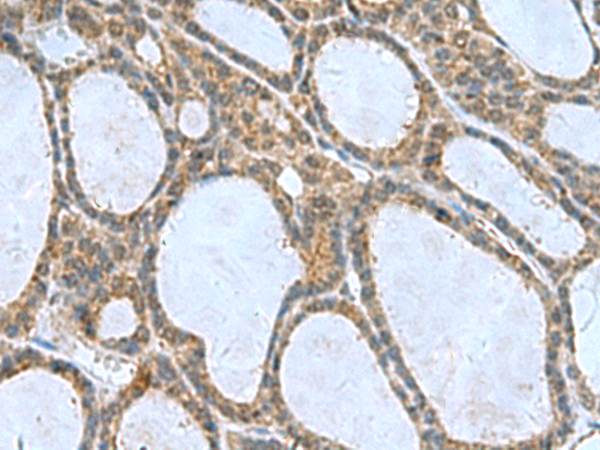

分类: 科研抗体货号: P10252别名: S16应用: IHC反应种属: Human, Mouse, Rat